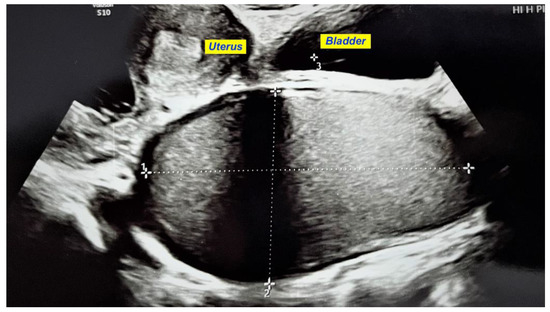

We present a case of HWWS diagnosed in our department in a 16-years-old girl who presented for severe left-lower quadrant pain, nausea, and urinary symptoms. Her menarche started the year before presentation, and monthly bleeding was regular; lasting 4 days; and was accompanied by increasing abdominal pain, nausea, urinary symptoms, and sometimes vomiting. She was not sexually active. During her first gynecology referral from another institution, she was recommended contraceptive pills for severe dysmenorrhea, which she refused. In the first visit in our hospital, the physical examination of the abdomen revealed mild abdominal tenderness of the left lower abdominal quadrant. Abdominal ultrasound (US) was performed but was considered not sufficiently informative; we only observed a voluminous cystic mass corresponding to hematocolpos. Therefore, after a careful explanation of the procedure and counseling, the girl and her parents decided to accept trans-rectal US examination. This revealed a didelphys uterus with a mild hematometra of the left hemiuterus, normal right hemiuterus and an impressive left-side collection, inferior and in connection with the left hemiuterus, corresponding to a hematocolpos. Both ovaries were present and of normal aspect and size (Figure 1). To better describe the findings and in view of the frequent association of congenital anomalies of the reproductive system with renal anomalies, an MRI was recommended and performed. The pelvic MRI showed two clearly separated hemiuteri (didelphys uterus), with mild left hematometra and normal right hemiuterus, mild left hematosalpinx, and an impressive left hemivagina, connected to the left hemiuterus, distended by a content whose signal was similar to methemoglobin, suggesting an obstructed hematocolpos (Figure 2A,B). Blood analysis was within normal range, except CA 125, which measured 89, 62 u/mL (more than the normal range for that age).

Figure 1. Transrectal US showing an impressive left hematocolpos and didelphys uterus with a mild hematometra of the left hemiuterus.